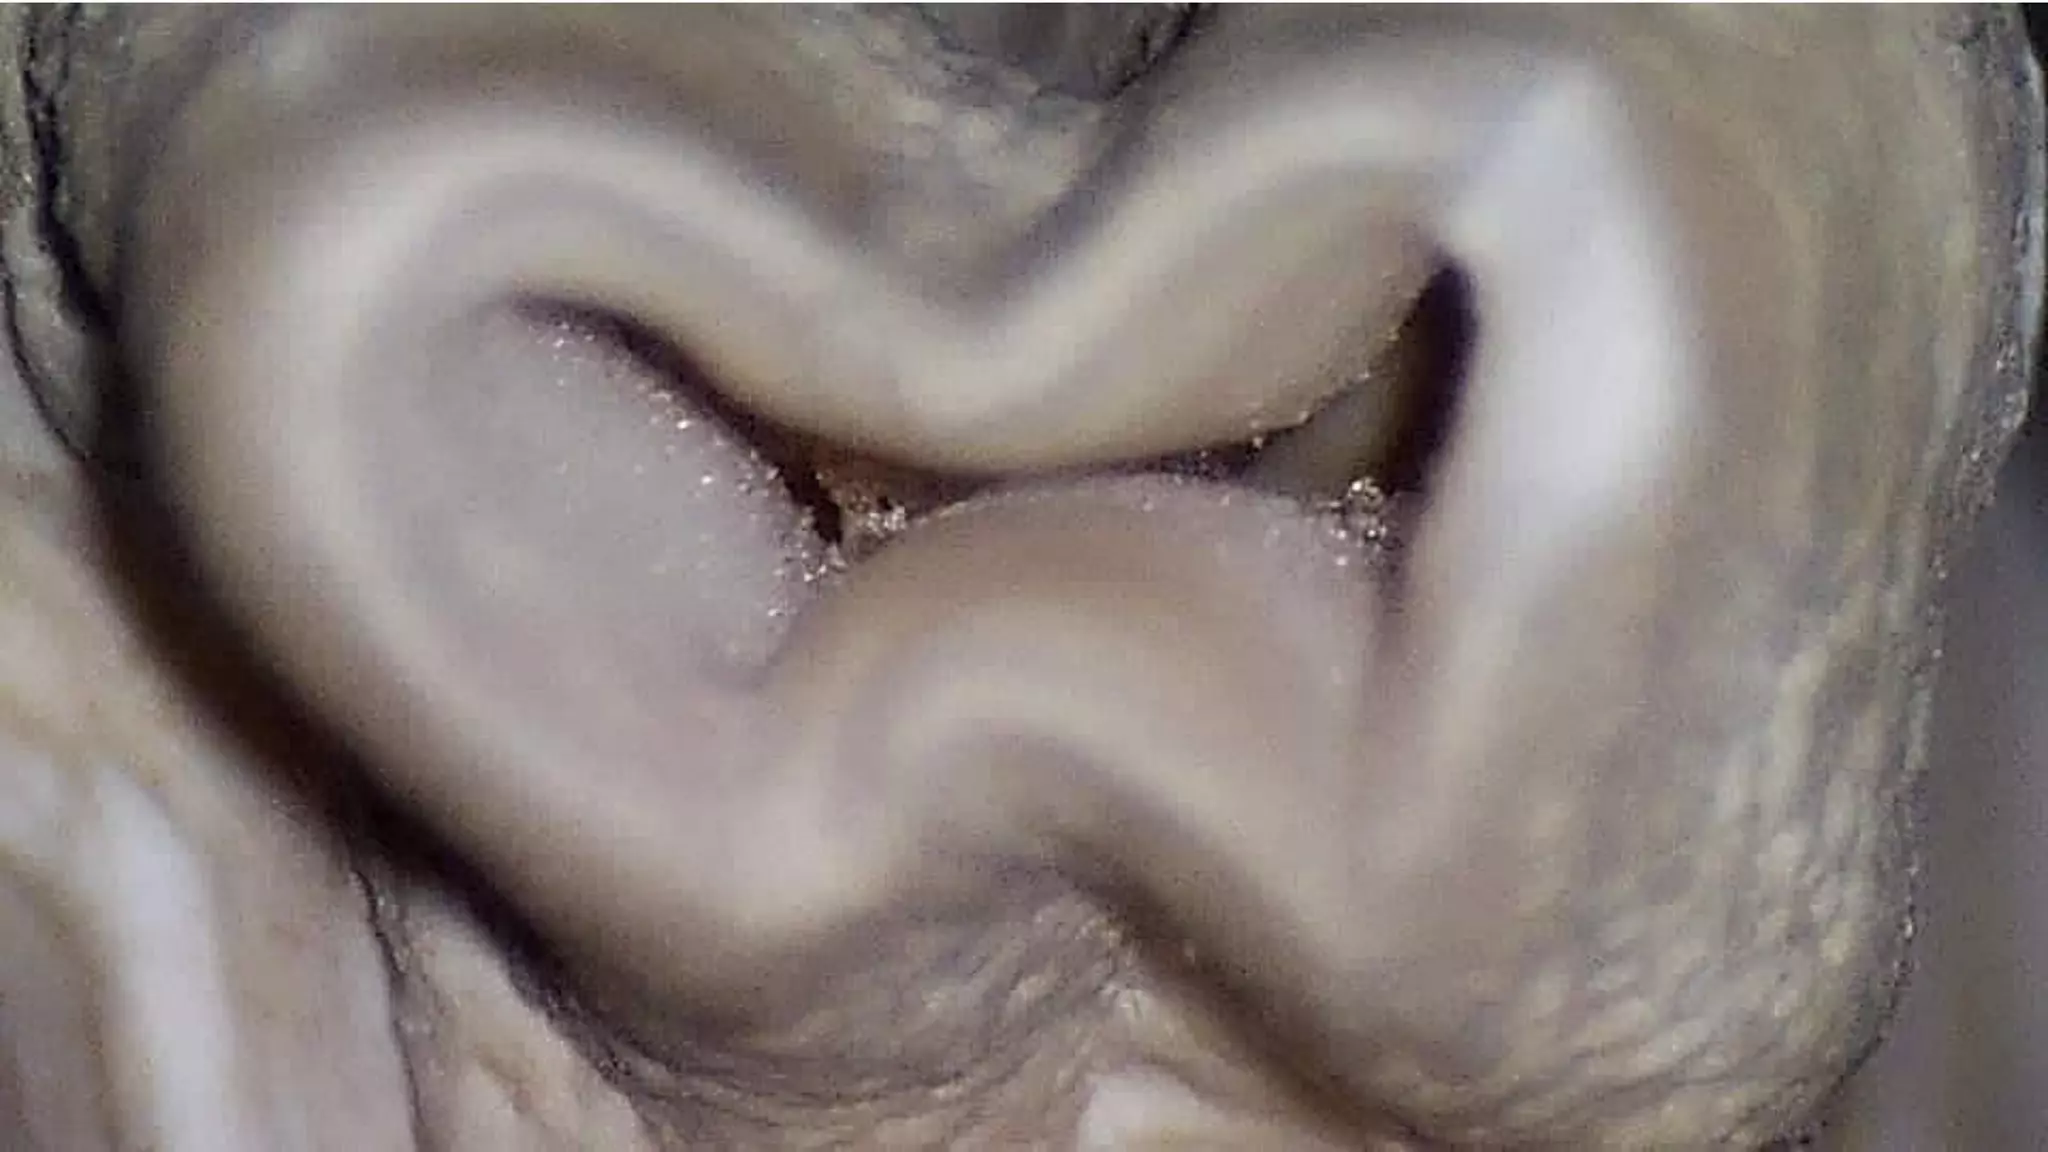

They include round, ribbon or figure eight, ovoid, bowling pin, kidney bean, and C shape.

With the exception of the round morphologic shape, each presents unique problems f

or adequate cleaning and shaping.

A, Round. B, Ribbon-shaped (hourglass). C, Ovoid.

D, Bowling pin. E, Kidney bean-shaped. F, C-shaped.

Types

Type•I

Incomplete isthmus; faint

communication between two

canals.

Type• II

Characterized by two canals with

definite connection between

them.

Type• III

Very short complete isthmus

between two canals.

Types. IV

Complete or incomplete isthmus

between two or more canals.

Type. V

Marked by two or three canal

openings without visibleconnections